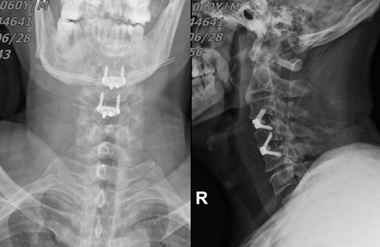

主要的辅助检查(图1-3):颈椎正侧位+张口位:未见明显颈椎骨折及脱位。颈椎MRI:1、颈脊髓损伤;2、C3/4急性椎间盘损伤伴前纵韧带损伤。头颅MRI:未见明显异常。颈椎CT:未见明显颈椎骨折及脱位。

图1:颈椎的张口位及侧位片

入院后完善相关检查,排除手术禁忌症,在全麻下行颈前路C3/4,C4/5椎间减压植骨融合术。术中见C3/4阶段前纵韧带断裂,周围组织水肿,C3/4椎体不稳,伴C3/4椎间盘突出,髓核游离。术后予抗头孢唑林钠感染、奥美拉唑护胃、七叶皂苷钠消肿、凯纷止痛、葡萄糖水补液、营养支持等,术后配合中频脉冲电疗促进神经功能恢复,下肢气压治疗,防止下肢静脉血栓形成。术后复查见图4。

图4,术后复查片。

影像学方面: 常规X线检查可发现该类病人存在颈椎曲度变直甚至反弓、颈椎管狭窄、OPLL、椎体或钩椎关节边缘骨赘、畸形等,过伸位、过屈位X线可显示是否存在颈椎失稳。该患者术前X线颈椎变直,增生退变明显。 CT检查可显示颈椎间盘突出、OPLL、黄韧带肥厚、骨赘形成、椎管容积欠缺等改变,CT影像三维重建可更加直观展现病变范围,有助于手术入路的设计。

该病例入院常规予激素抗炎、甘露醇消肿脱水,枕颌带牵引,完善术前检查,入院后2天左右行手术治疗。我们采用颈前路手术,主要考虑压迫主要是椎间盘突出引起的,同时采用损伤较小的颈椎前路零切迹椎间融合器。 颈椎前路零切迹椎间融合器是一种具有支撑、固定及融合功能的新型材料,同时具备椎间融合器和前路固定钢板的优点。颈椎前路零切迹椎间融合手术具有切口小,只需要处理椎间隙处前纵韧带,减少邻近阶段韧带及椎间盘损伤继发退变的风险。零切迹椎间融合器具有良好组织相容性,生物性能稳定,可透X线检查,方便术后随访。零切迹融合器植入后被包容在椎间隙内,不超过椎体前缘,做到与食管无接触,对食管无**,减少了颈前路最常见并发症术后吞咽不适的发生。其安装较简单,上下各有两处固定锁定钉道,头端锁定钉在外,尾端锁定钉在内,可以实现上下多阶段融合固定,螺钉拧入时,可保证螺钉在椎体骨质内,不进入椎间隙,具有较强的稳定性。

总之,零切迹椎间融合器具有切口小,操作简单,生物力学稳定性良好,减少邻近阶段退变发生率等特点,因此具有颈椎前路钢板及椎间 融合器联合应用的优势。本病例中采用零切迹椎间融合器,患者术后吞咽不适感明显减少,食管**少,患者满意度提高。同时内固定物固定牢靠,未见松动、移位,脊髓功能获不同程度改善。